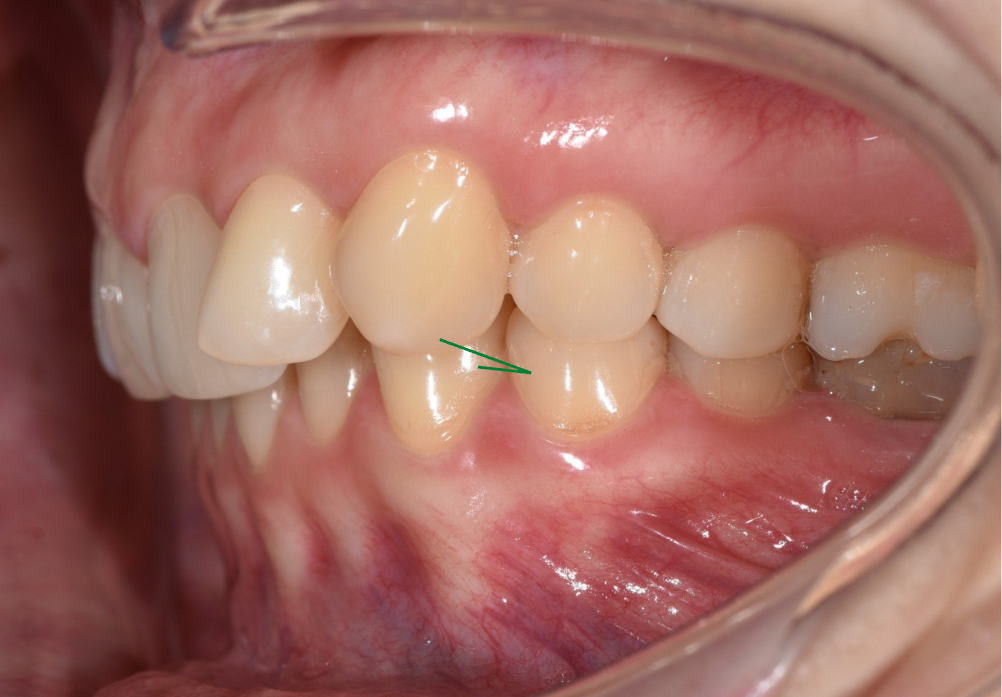

У пациентки, кейс которой мы сегодня рассматриваем, было очень большое несоответствие по контактам – это значит, что верхний зуб неправильно смыкался с нижними, контактируя не с двумя антагонистами, как положено, а заходя на другие зубы.

По этой фотографии видно, что несоответствие у нас больше, чем на половину зуба – зеленой стрелочкой показано, на какие зубы должен заходить клык.

клык ушел сильно вперед, смыкаясь только с одним зубом на верхней челюсти.